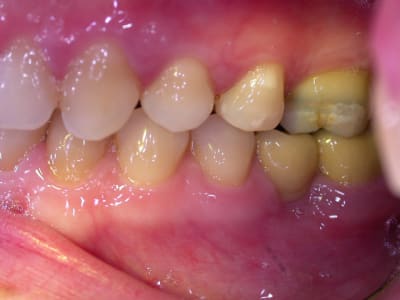

examen buccal .........voir les photos ........après ........ca vient

Bon controle de plaque, pas de tartre ni de colorations, inflammation en palatin seulement...